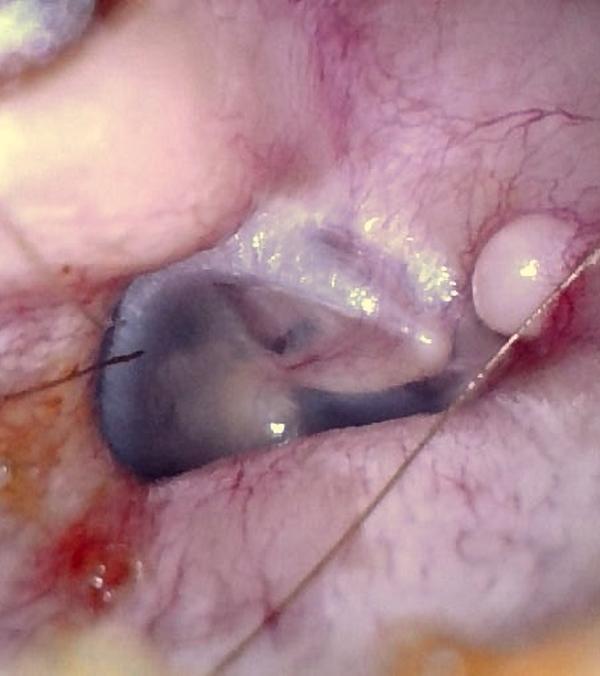

Surfer’s Ear (Exostoses)